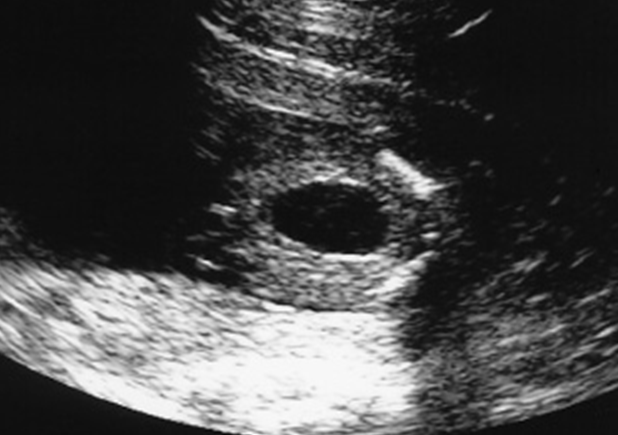

Urachal cyst